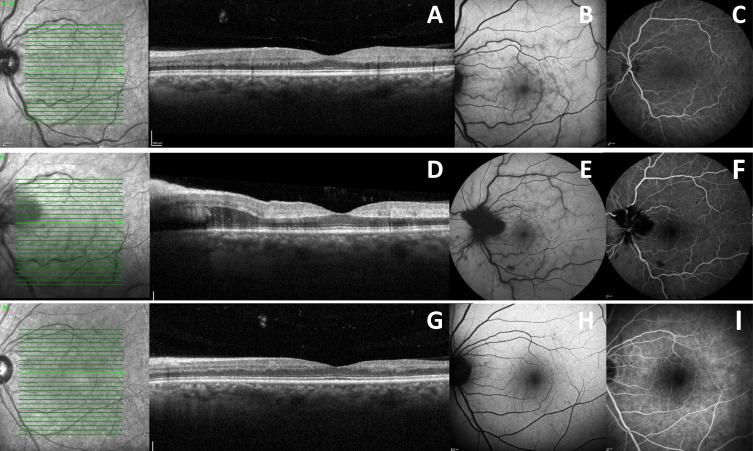

新冠病毒感染及新冠疫苗接种后的视网膜变化

CASE PRESENTATION

In this article, a series of clinical cases with retinal vascular alterations after COVID-19 infection and vaccination are described.

严重急性呼吸综合征冠状病毒2(SARS-CoV-2)疾病于2019年首次报告,最初与呼吸道病理学相关。随着对该疾病认识的提高,人们注意到,在其他症状中,一些患者出现了与视网膜血管变化相关的视力变化,主要与血栓形成现象有关。后来,随着针对SARS-CoV-2疾病疫苗的研发,也报告了血栓形成现象继发的视力改变病例。

病例报告

本文描述了一系列新冠病毒感染和接种疫苗后出现视网膜血管改变的临床病例。